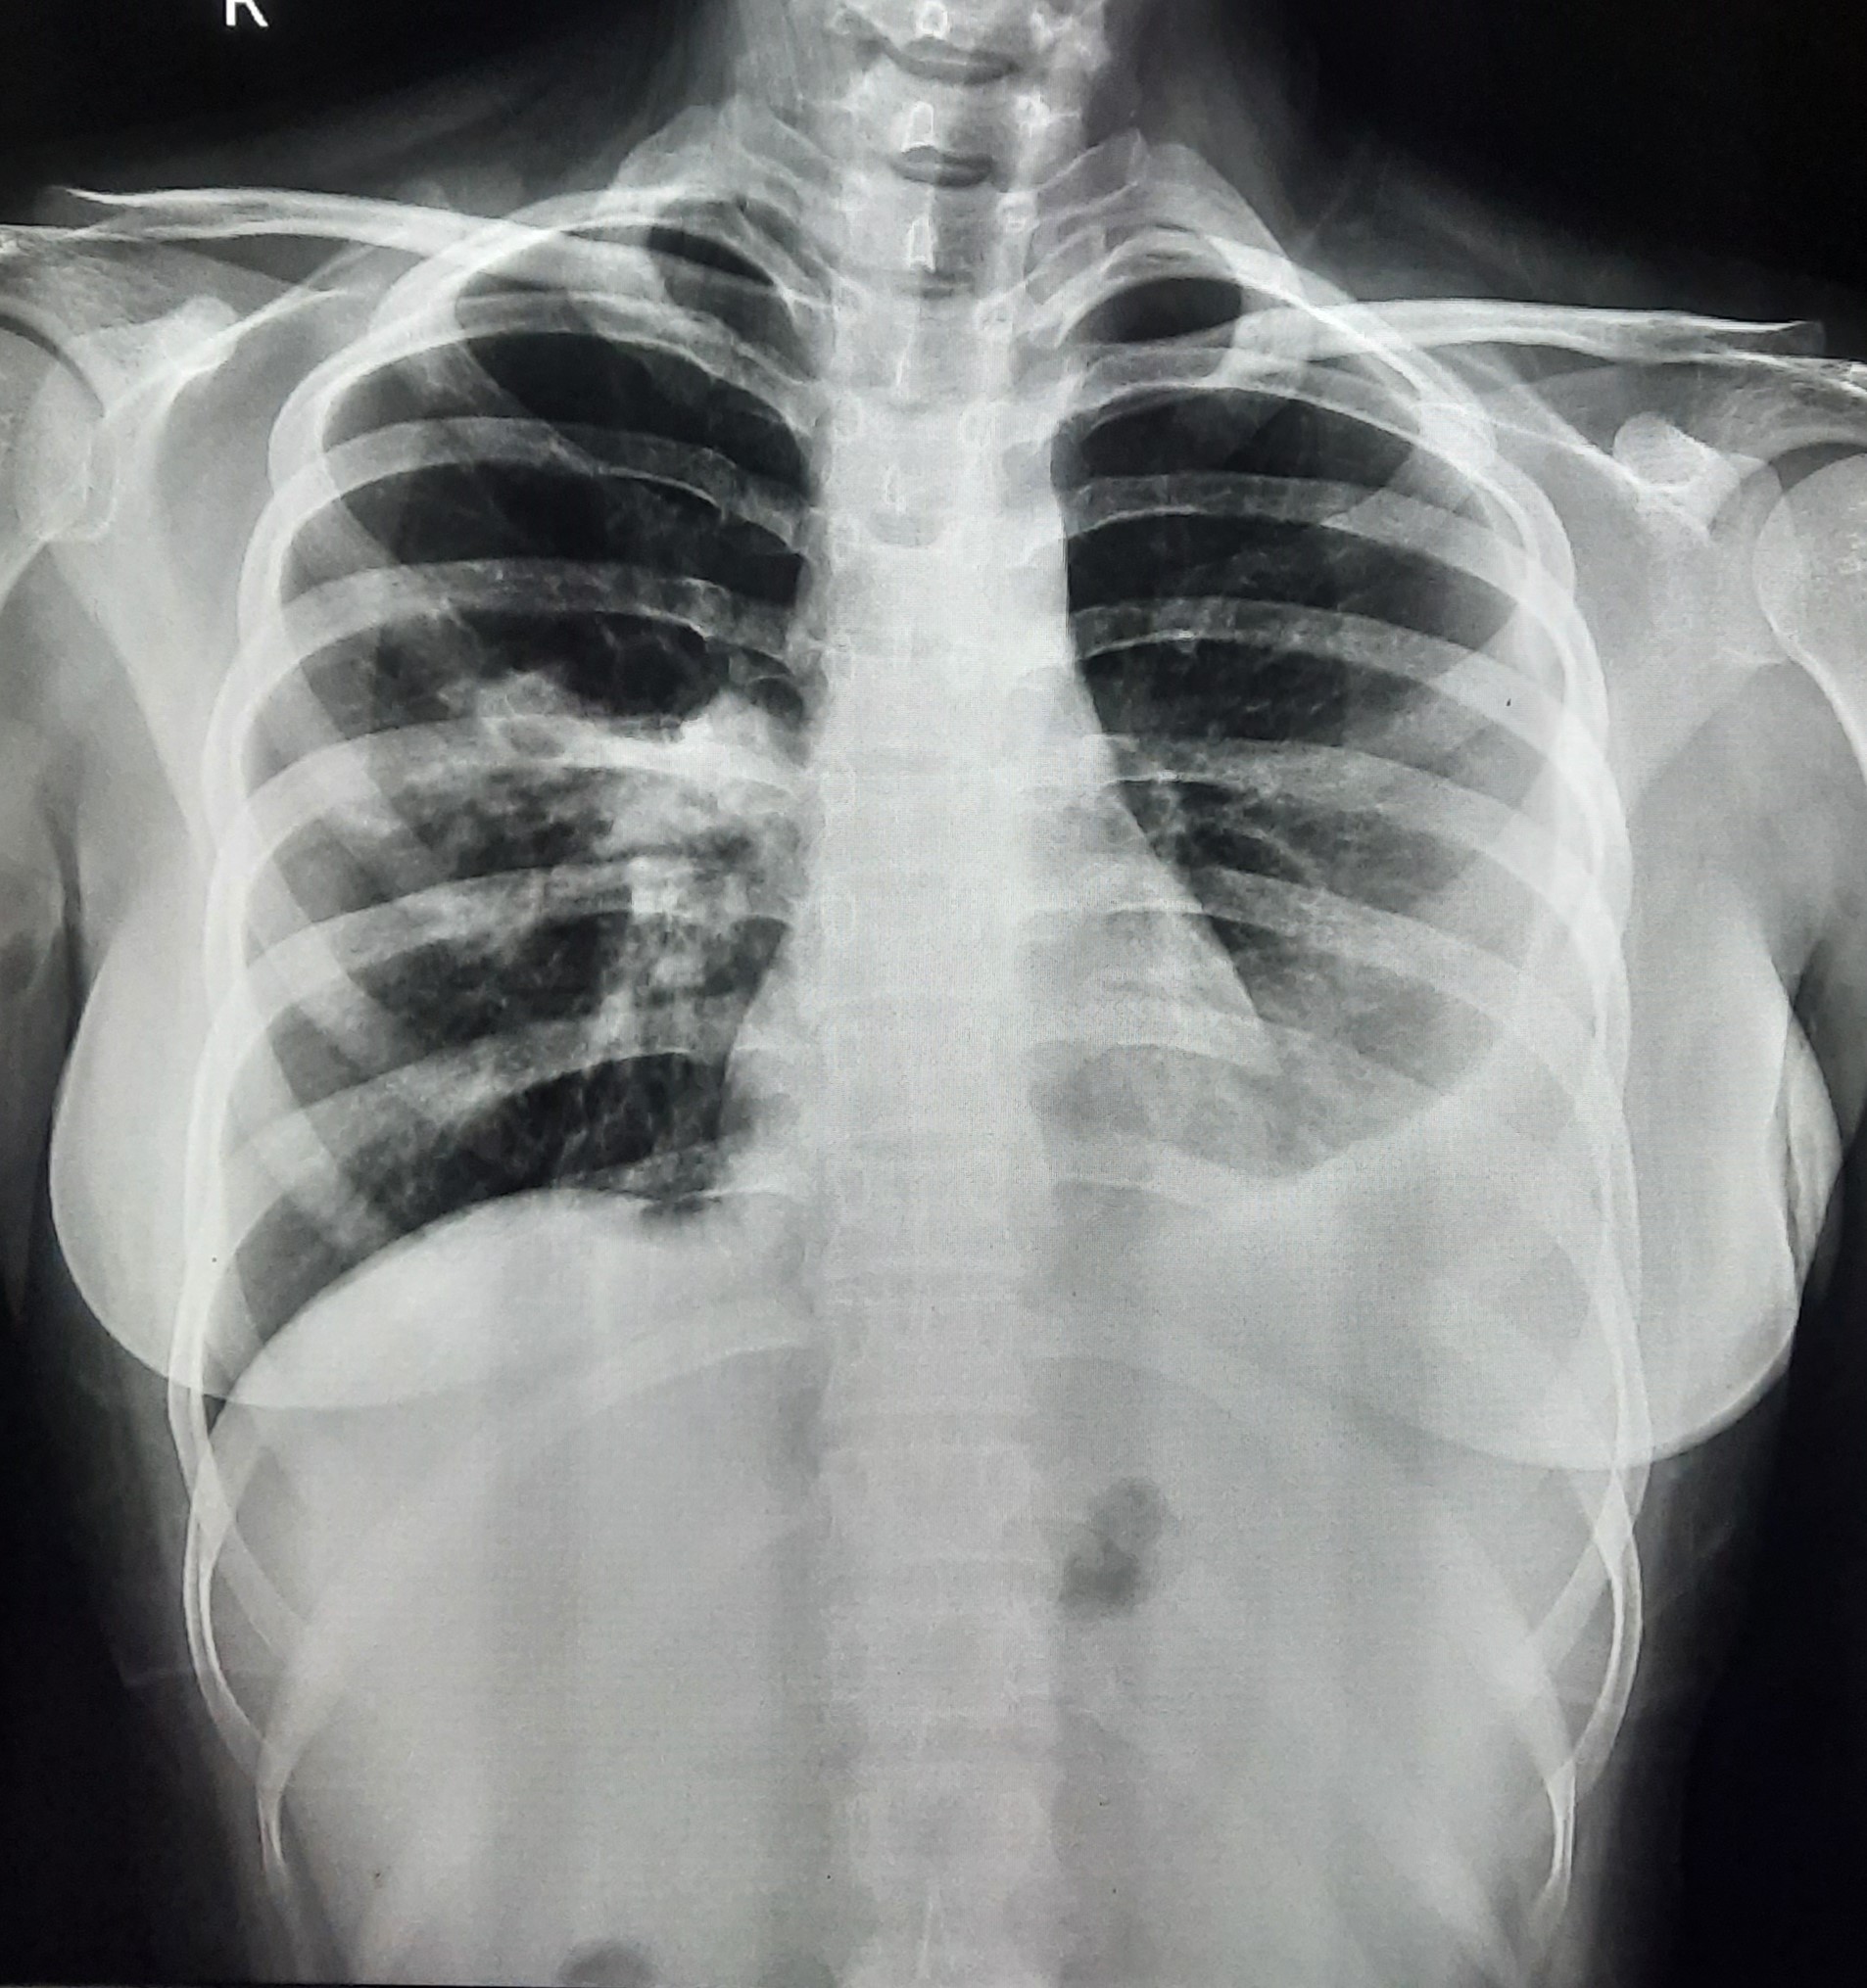

| 84 | IGGMC, Nagpur, Nagpur | P2 | 29-4388 | Dipak Panchbudhe | Consent taken on Paper | 33 Yrs. |

Provisional Diag : Pulmonary Tuberculosis Reactivation ?

Final Diag : Pulmonary Tuberculosis |

TB Case (Confirmed) | Bilateral multiple ill-defined alveolar opacity present, Left Sided Upper Zone Fibro Cavitary Lesion Present | Abnormality visible on x-ray |